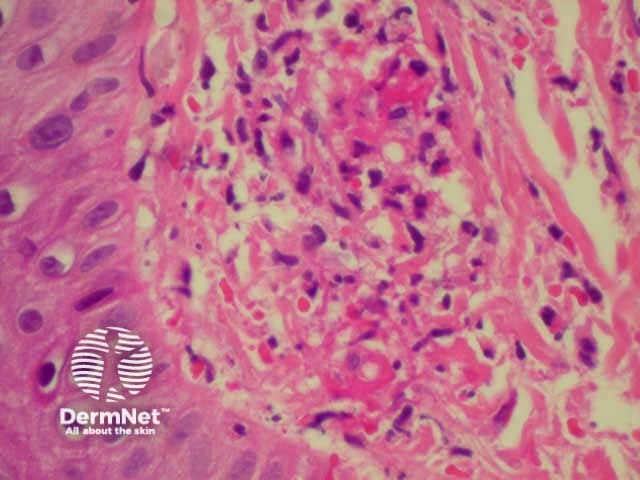

Dermatopathology shows a necrotising vasculitis.

Dermatopathology of hypersensitivity vasculitis Dermatopathology of hypersensitivity vasculitis